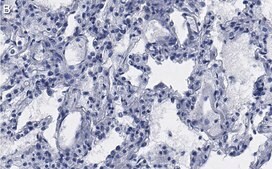

Immunohistochemistry (Paraffin) Analysis: A 1:100 dilution from a representative lot detected CD54 in human lung tissue sections.